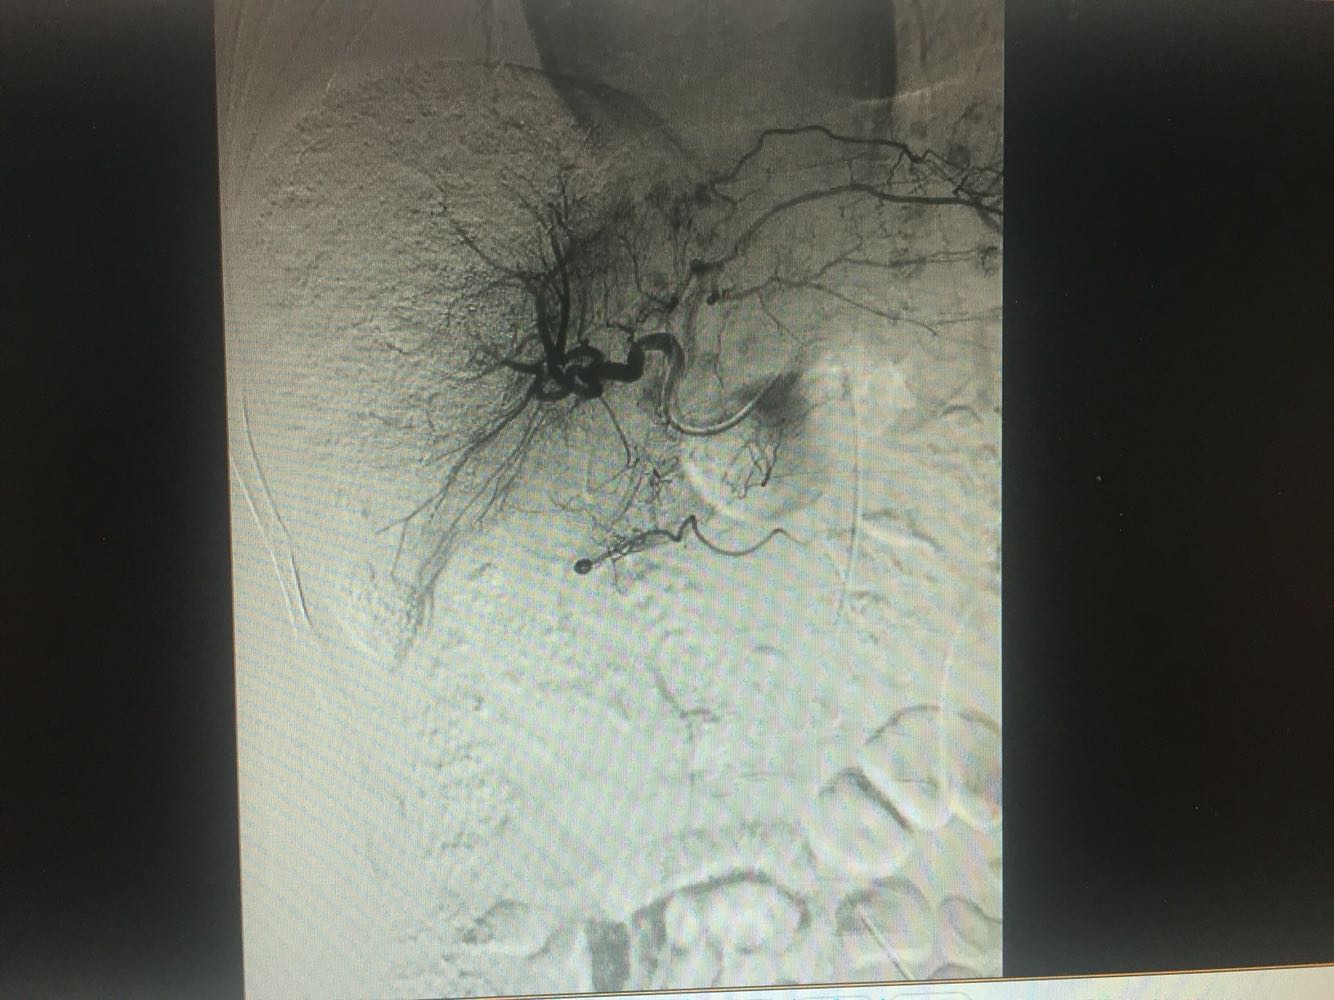

乙肝肝硬化,原发性肝癌,保肝抗病毒治疗,及TACE

出院一月后复查,行增强CT扫描,肿瘤明显缩小,肝功能正常,乙肝病毒复制转阴,建议继续口服恩替卡韦抗病毒治疗